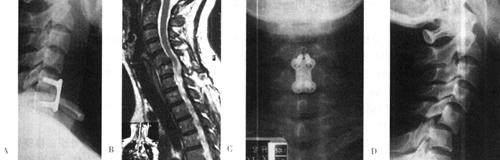

图13-12 42岁女性,C5~C6脱位,前路CSLP固定